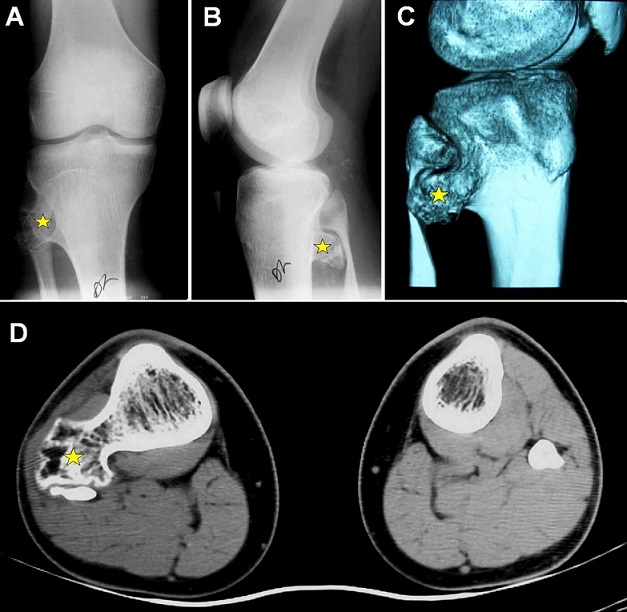

A 15-year-old adolescent, previously healthy, presented with right peroneal nerve palsy sustained after a direct closed knee injury in a soccer game. The physical examination revealed a marked weakness to dorsiflexion of the right ankle and toes without sensory loss. A bony mass was noted in the right postero-lateral area of the knee. Plain radiographs and a computed tomography-scan of the knee showed a large osteophytic mass in the proximal metaphyse of the right tibia with an important mass effect on the fibular head which is deformed (A-D). Electrophysiological studies confirmed denervation of the muscles supplied by the right peroneal nerve. The patient underwent surgical decompression of the nerve after resection of the osseous mass. Postoperatively, there was a progressive improvement of the nerve function. The patient was referred for physiotherapy care. Histological features were consistent with benign osteochodroma. Osteochondromas (exostosis) frequently develop around the knee in the distal femur and the proximal tibia and fibula. These osteocartilaginous tumors are usually asymptomatic, but can occasionally impinge on the surrounding nerves and vessels and cause various clinical manifestations. Tibial osteochondroma compressing both the fibular head and the peroneal nerve is rarely seen especially following a direct injury.